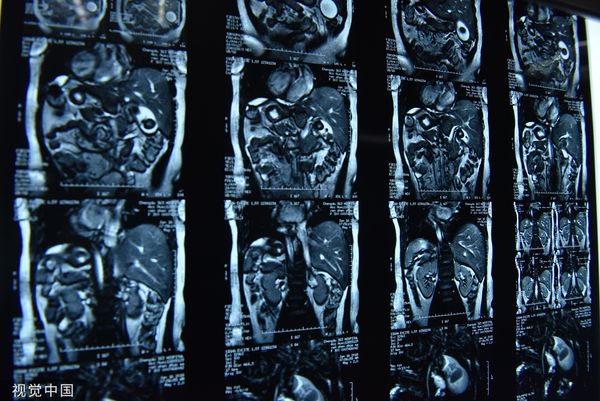

武汉出现罕见“镜面人”宝宝 百万分之一几率“内脏左右相反”

中国武汉一间医院近日接生一名罕见的“镜面人”宝宝,这名宝宝的心脏、脾脏位于身体右侧,肝脏位于左侧,与一般人的脏器位置相反。经过5天的照顾,宝宝父亲抱着小男婴和妻子顺利出院,同时向医护团队的悉心照料表示感谢,这才让这名百万之一几率才会出现的“镜面宝宝”被外界知晓!

25岁的镜面人宝宝小雯(化名)是在武汉大学中地医院妇儿医院产检时,在医生检查胎儿内脏结构和形态时发现,胎儿的心脏、肝脏、脾脏、胆的位置刚好与一般胎儿相反,仿佛正常脏器的镜像,因此判定胎儿是个“镜面宝宝”。